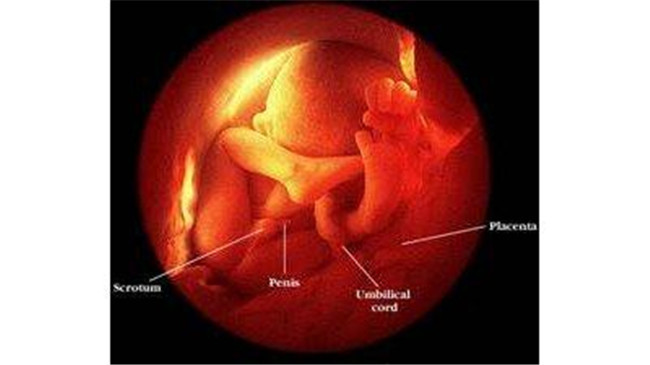

如果是男婴,从四个月开始就能够从B超中看到他的男性特征了。

在八个月时,胎儿男婴的*丸睾**已经从腹腔下降落入了他的阴囊内,但是有的男婴的*丸睾**是出生当天才进入阴囊的,有的因为发育迟缓问题,出生后还没有进入的,就要进行治疗了。

胎儿这个时候的指甲已经长出来了挺长的,皮肤是淡红色,比较光滑,但脸仍然充满皱纹。

宝宝能够在子宫里转来转去。胎儿现在长得越来越大,孕后期是胎儿增长最快的时候,身体几乎占据了整个子宫,所以胎动会逐渐的减少。

身长已经达到40到45厘米,体重增长到1400到2100克,已经具备了在子宫外生活的能力,但是仍然要注意,因为肺部还没发育完全,所以这个时期需要保重身体,避免早产。